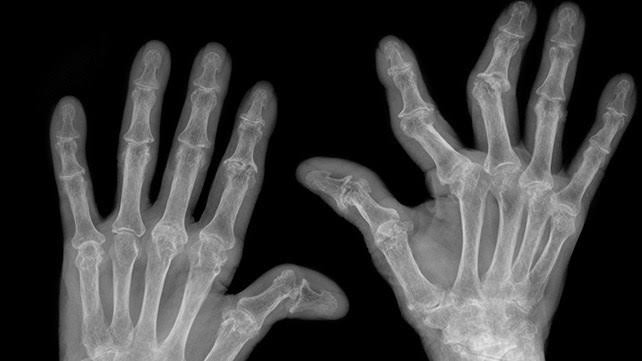

Featured photo from healthline.com

I went to a new exercise class to try it out. Told the instructor I have Rheumatoid Arthritis (because that’s what you do in these circumstances, they need to know).

Her: ‘Oh but YOUR hands aren’t like hers!’ (Implying I don’t have as serious a case of RA as her example)

Me: ‘That’s because I was a nurse when I was diagnosed and knew to strap my hands so they wouldn’t get deformed. And also, I exercise. Back in the day, doctors would tell you to go home and rest, now they tell you to keep moving. Which is why I’m here.’